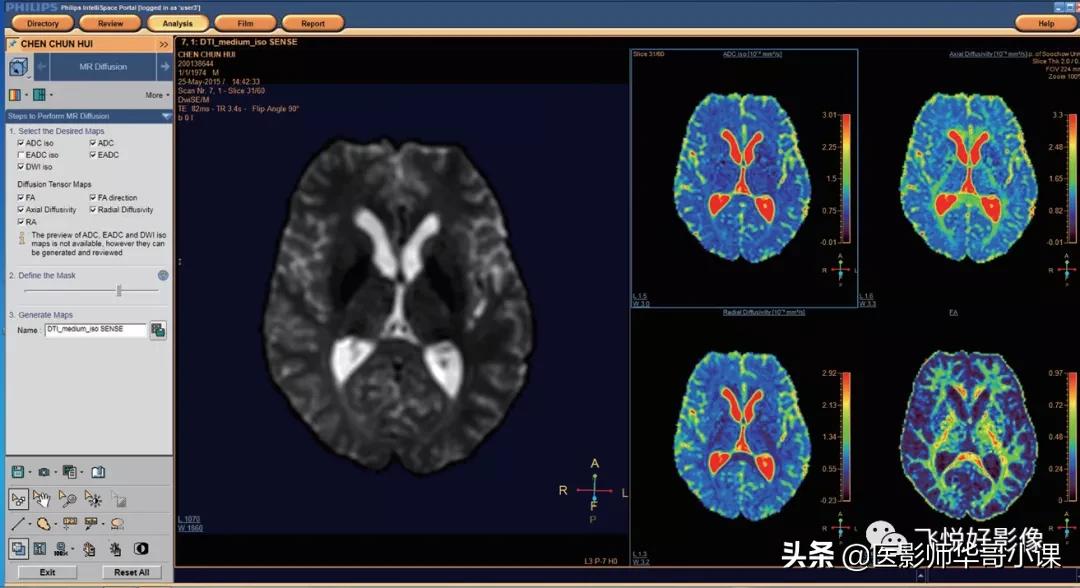

在 Intellispace Portal 上选择有效的 DWI、DTI 序列(如图1)。

图1.DWI&DTI

选择需要的视图:在图8左侧栏中选择需要视图,并打勾,DTI序列可选择FA相关视图。

图8.选择视图

选择视图后,继续进行第二步操作,对图像背景噪声进行遮噪(图9箭头所示)。遮噪时注意不能过度遮噪,掩盖扫描的组织图像。

图9.选择遮噪